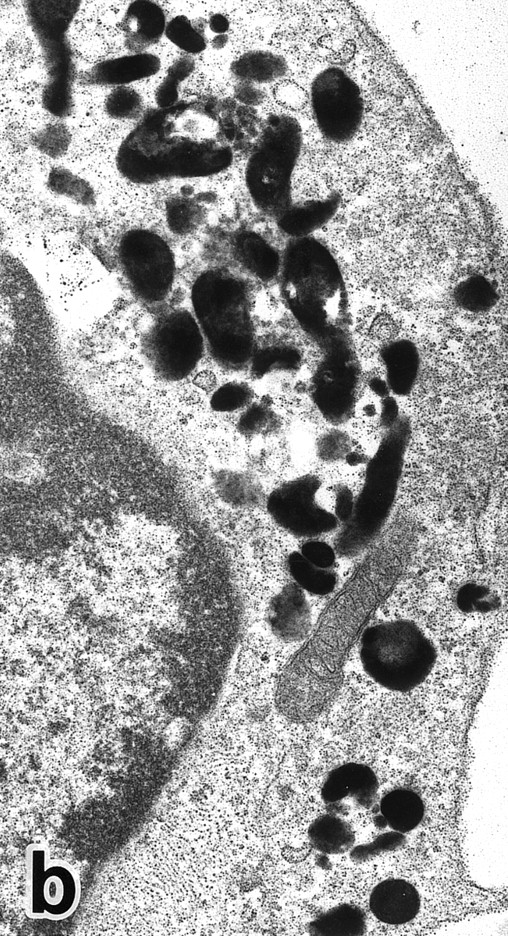

(a) A PMN in patient no. 2 after 10 days of ATRA treatment. The nuclei are irregularly lobulated, with some of them being connected by nuclear filamentous structures, and heterochromatin is condensed along the nuclear membrane. (Original magnification × 13,100.) (b) Higher magnification of a portion of the cell in (a). The cytoplasmic granules are large and spherical, and some of them contain flocculent material and central cores with higher electron density. (Original magnification × 20,200.)

Common morphological changes of bone marrow leukemia cells were observed during ATRA treatment. After 1 week of ATRA treatment, leukemic cells showed heterochromatin condensation and nuclear lobulation (Figs 3 and 4). Although the lobulated nuclei of some cells resembled those of PMNs, these nuclei were irregular in shape and nucleoli were occasionally present. The lobulated nuclei often had nuclear blebs (Fig 3a) or were connected by thin nuclear material (Fig 4a), called filamentous connections,13 that consisted of heterochromatin delimited by the nuclear membrane. In addition to these changes, the irregularly shaped primary granules became morphologically normal. This was most evident in patient no. 1, in whom the majority of both Auer rods and irregularly shaped inclusions, as shown in Fig 2, dramatically vanished and the remaining primary granules appeared normal, being spherical in shape and relatively homogeneous in size (Fig 3a), although abnormal primary granules and/or Auer rods were infrequently observed in some cells. Rarely, a structure composed of an Auer rod coupled with a primary granule was found, appearing as though the seemingly normal primary granule had emerged from the Auer rod (Fig 3b). Type I primary granules still predominated in all patients, but type II primary granules with a nucleoid structure were rarely observed in patients no. 1 and 2. Some maturing neutrophils with abnormally shaped lobulated nuclei in patient no. 2 possessed unusual, possibly immature, primary granules containing central electron-dense material (Fig 4a and b), indicating asynchronous maturation of nuclei and cytoplasmic granules.